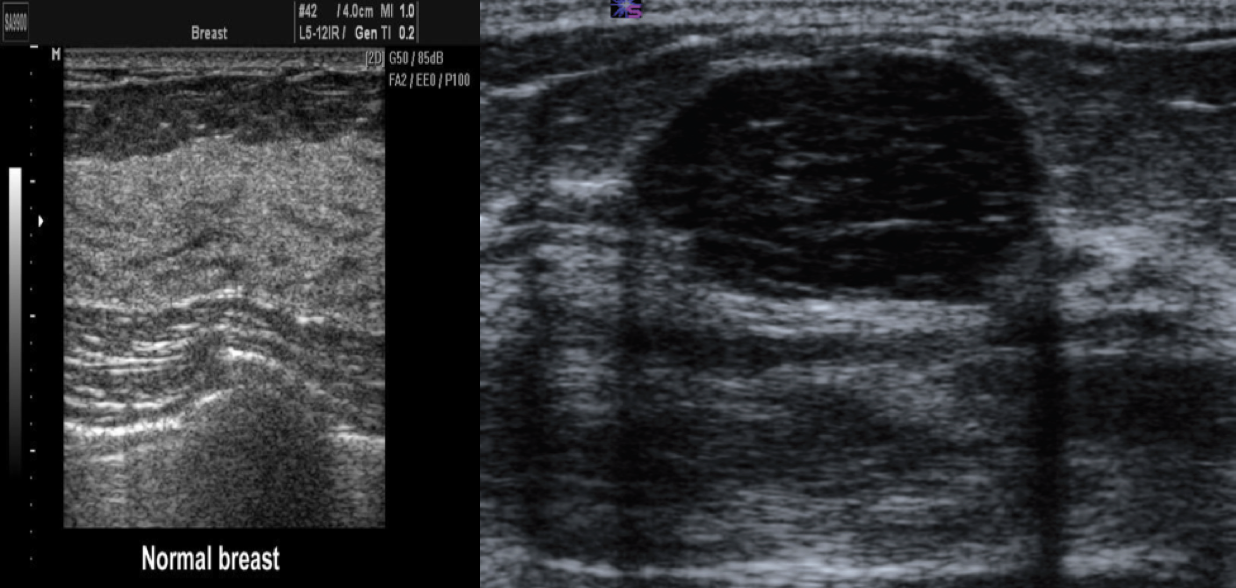

In postmenopausal women and women ℠30 years of age with a suspicious breast mass, mammography is preferred over ultrasound Z . In premenopausal women < 30 years of age, ultrasound is preferred Z , because the higher density of breast tissue decreases the diagnostic power of mammography.

Ultrasound image of a benign breast lesion. There is a very well-defined hypoechoic ovoid mass typical of a benign fibroadenoma.

Breast Ultrasound is usually done to differentiate between solid and cystic masses